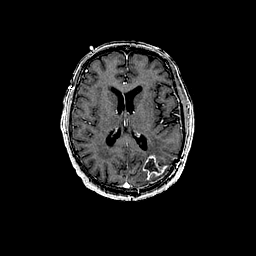

Glioma overlay -- Slice #66

[Home][Help][Clinical] Slice 66